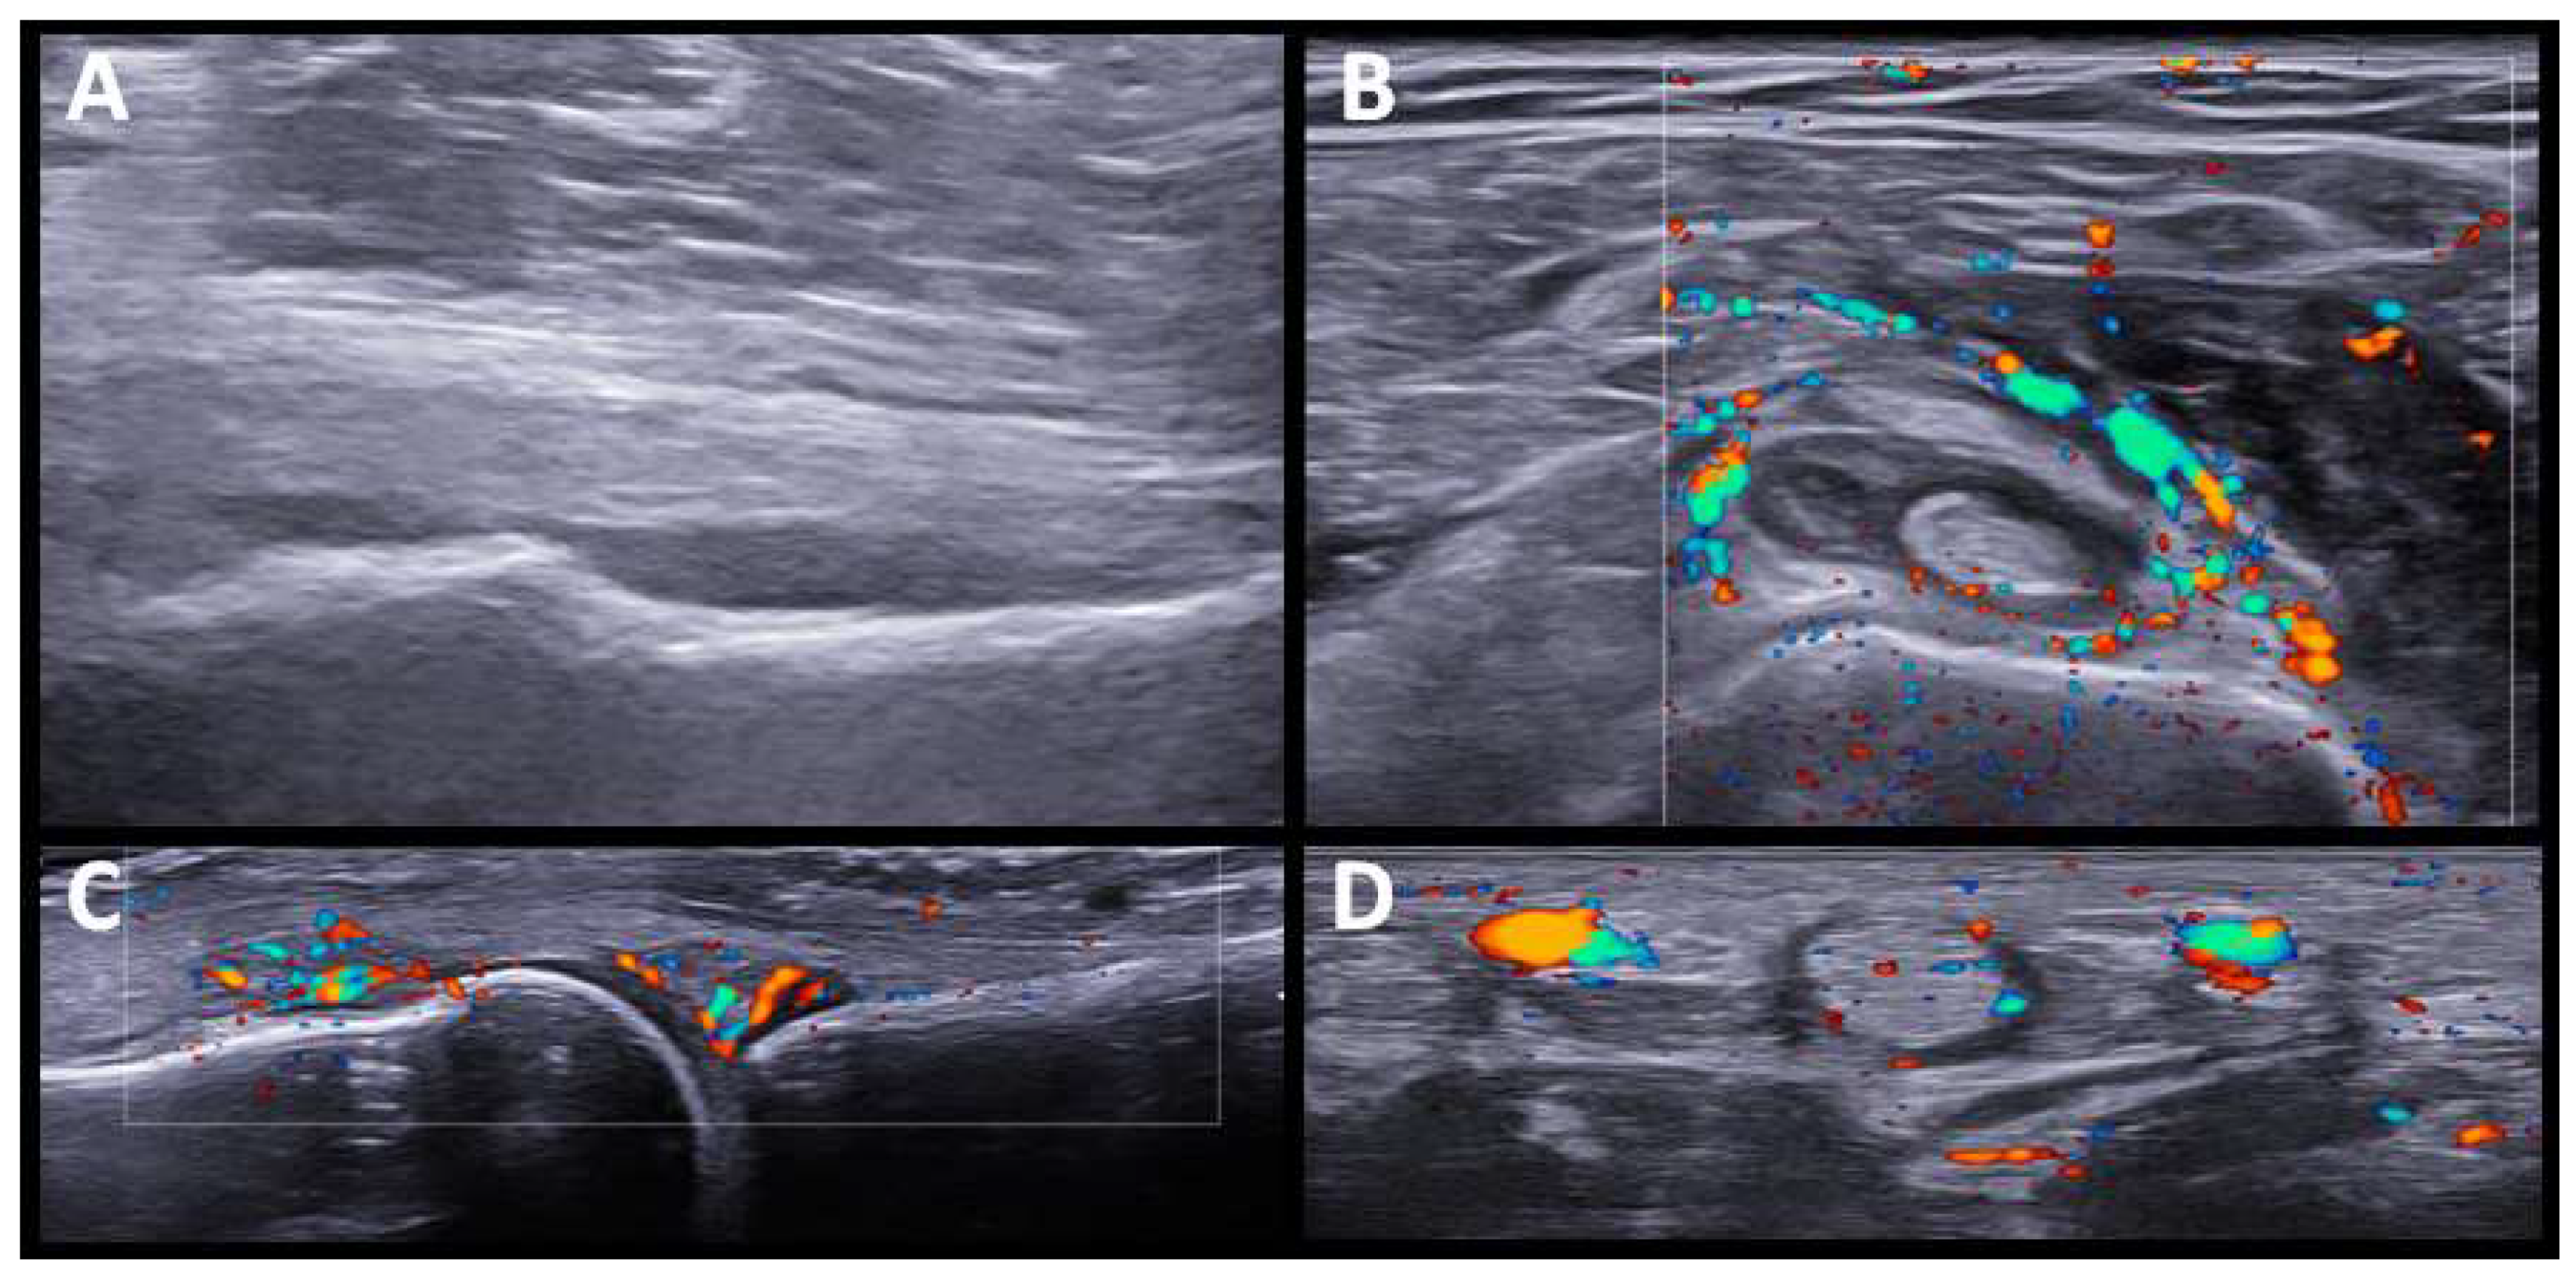

Five patients had a PMR-like syndrome. In three, the imaging test was made before the start of glucocorticoid treatment. US showed synovitis of the hip and trochanteric bursitis, and bilateral inflammatory bicep tenosynovitis, in one patient. In the other two patients, the shoulders and hip joints were studied by PET/CT scan, showing a periarticular pattern in the shoulder and pelvic girdle (see further comments below). We also identified sonographic changes in the wrists and hands in patients with PMR-like disease, affecting not only the wrists but also the MCPs, and finger tenosynovitis (Figure 2).

Figure 2.

US findings in PMR-like pattern. (A). Hip joint (longitudinal view) with moderate effusion. (B). Bicipital tenosynovitis with power doppler signal grade 2. (C). Synovitis at second MCP joint with Power Doppler grade 2. (D). Tenosynovitis of hand flexor tendon with Power Doppler grade 2.

It has been reported that ICI-induced PMR has US and FDG-PET/CT results comparable to those seen in regular PMR [26]. We also found characteristic US findings in PMR-like ICI-induced patients similar to those previously described (i.e., glenohumeral and hip joint synovitis, bicipital tenosynovitis, and subacromial bursitis) [26]. Peripheral symmetrical synovitis and tenosynovitis, clinically subtle or not evident at all, in addition to rhizomelic involvement was a notable finding. Although peripheral synovitis and tenosynovitis are frequently reported in PMR, it is usually oligoarticular and transient [31]. As in other studies of typical PMR [32], we found that in patients with ICI-induced PMR, tenosynovitis of the flexor tendons of the hand was the most frequent US finding of peripheral involvement. Interestingly, in treated patients, we found not synovitis, tenosynovitis, or bursitis in the shoulders and pelvic girdles, which seemed to have resolved with glucocorticoid treatment. However, peripheral synovitis/tenosynovitis in the hand joints remained evident.